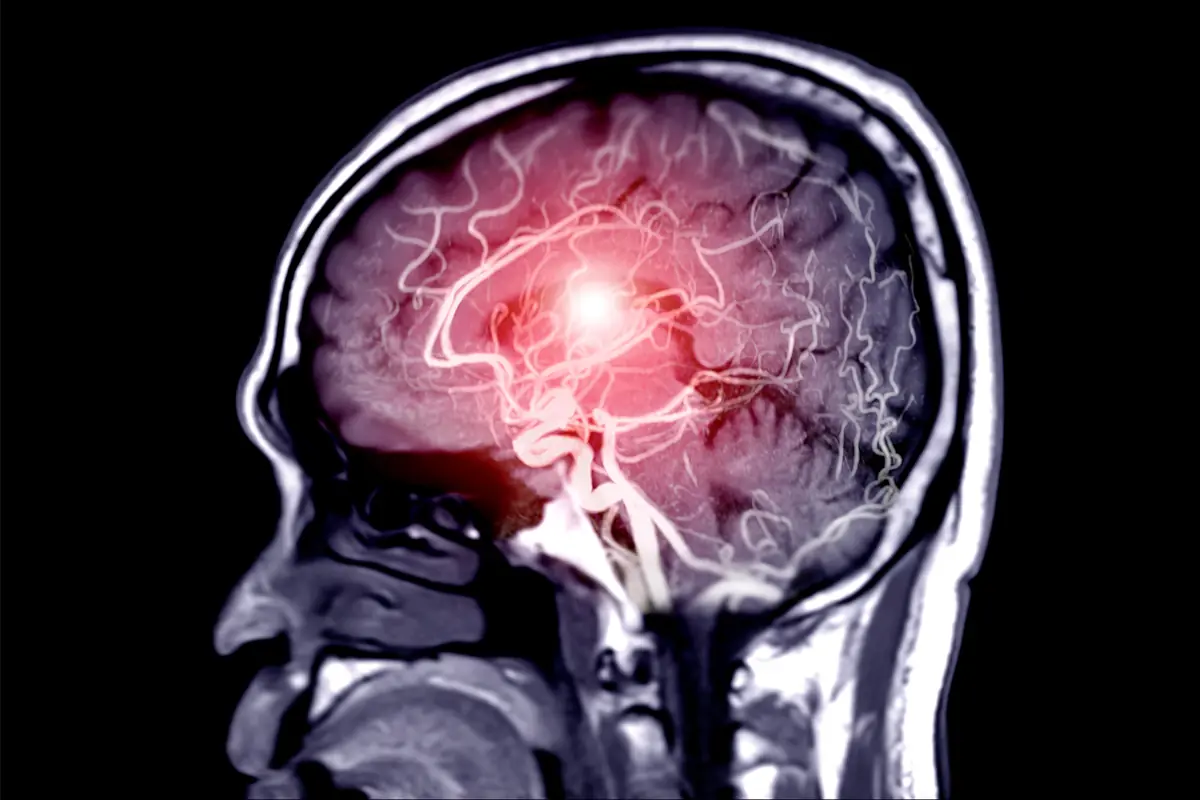

“หลอดเลือดสมองโป่งพอง” หรือ Aneurysm เป็นภาวะที่หลายคนอาจไม่คุ้นเคย แต่กลับเป็นภัยเงียบที่อันตรายถึงชีวิตได้โดยไม่ทันตั้งตัว ภาวะนี้เกิดจากผนังหลอดเลือดในสมองอ่อนแอและโป่งพองออก คล้ายลูกโป่ง เมื่อมีแรงดันมากขึ้น อาจแตกและทำให้เกิดเลือดออกในสมอง ซึ่งเป็นเหตุฉุกเฉินทางการแพทย์

ผู้เชี่ยวชาญด้านระบบประสาทระบุว่า ปัญหาสำคัญของโรคนี้คือ ในระยะแรกมักไม่มีอาการชัดเจน ทำให้ผู้ป่วยจำนวนมากไม่รู้ตัว จนกระทั่งเกิดการแตกของหลอดเลือด ซึ่งมีอัตราการเสียชีวิตและพิการสูง

แพทย์ยังเตือนว่า หากหลอดเลือดสมองโป่งพองแตก จะทำให้เกิดภาวะเลือดออกใต้เยื่อหุ้มสมอง (Subarachnoid hemorrhage) ซึ่งเป็นภาวะรุนแรง ผู้ป่วยอาจหมดสติ ชัก หรือเข้าสู่ภาวะโคม่าได้ภายในเวลาอันสั้น

สำหรับผู้ที่มีความเสี่ยงสูง เช่น มีประวัติครอบครัวเป็นโรคนี้ อาจพิจารณาการตรวจคัดกรองด้วยเครื่องมือทางการแพทย์ เช่น MRI หรือ CT scan เพื่อประเมินสภาพหลอดเลือดในสมอง